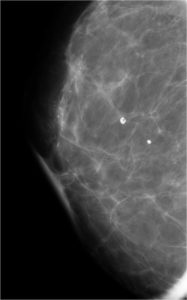

52 year old lady who underwent wide local excision for stage I breast carcinoma of right breast 7 years ago has presented for routine screening mammogram.

Ductal Cell carcinoma In Situ-DCIS RIGHT BREAST.(Comedo and cribriform type)

Craniocaudal and mediolateral oblique views of both the breast.Post operative scar is seen in the upper and outer quadrant of right breast.Pleomorphic calcifications,predominantly showing fine linear branching pattern( comedo pattern) is seen in segmental distribution with nipple convergence in the central right breast.